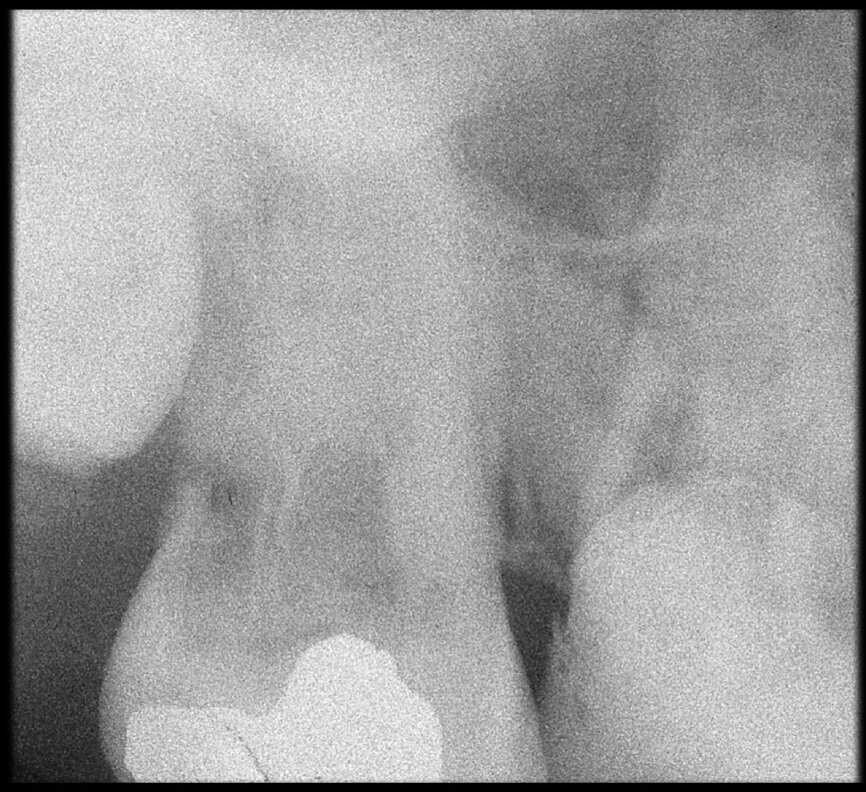

The case with which I would like to start my clinical review is a perfect example of how difficult it is to establish the origin of the patient’s symptoms on the basis of an intraoral radiograph alone. Not only does the 2D study fail to establish with certainty the presence of a lesion, but more importantly, it is impossible to establish the size, morphology and type of the lesion. An analysis of the 3D imaging, however, provides a clear picture of the clinical situation: the coronal and sagittal slices revealed the presence of a large lesion extending from the apex of the mesial root of this molar to the furcation, while the axial slices allow us to conduct a precise analysis of the endodontic anatomy and, in particular, the shape of the mesial root, which in this case was fused with the palatine root. A full overview of the case can, therefore, guide the decision-making process and direct the treatment plan towards a specific type of treatment (Figs. 1–4).